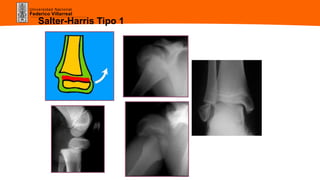

Cuales son las características radiológicas de un

desprendimiento epifisiario tipo I de SALTER y

HARRIS?

• Desprendimiento del cartílago de conjugación, sin fractura.

• Desplazamiento escaso a veces, o moderado, o completo

con perdida de contacto.

• Interposición del periostio, con bostezo persistente post-

reducción

Salter-Harris Tipo 1